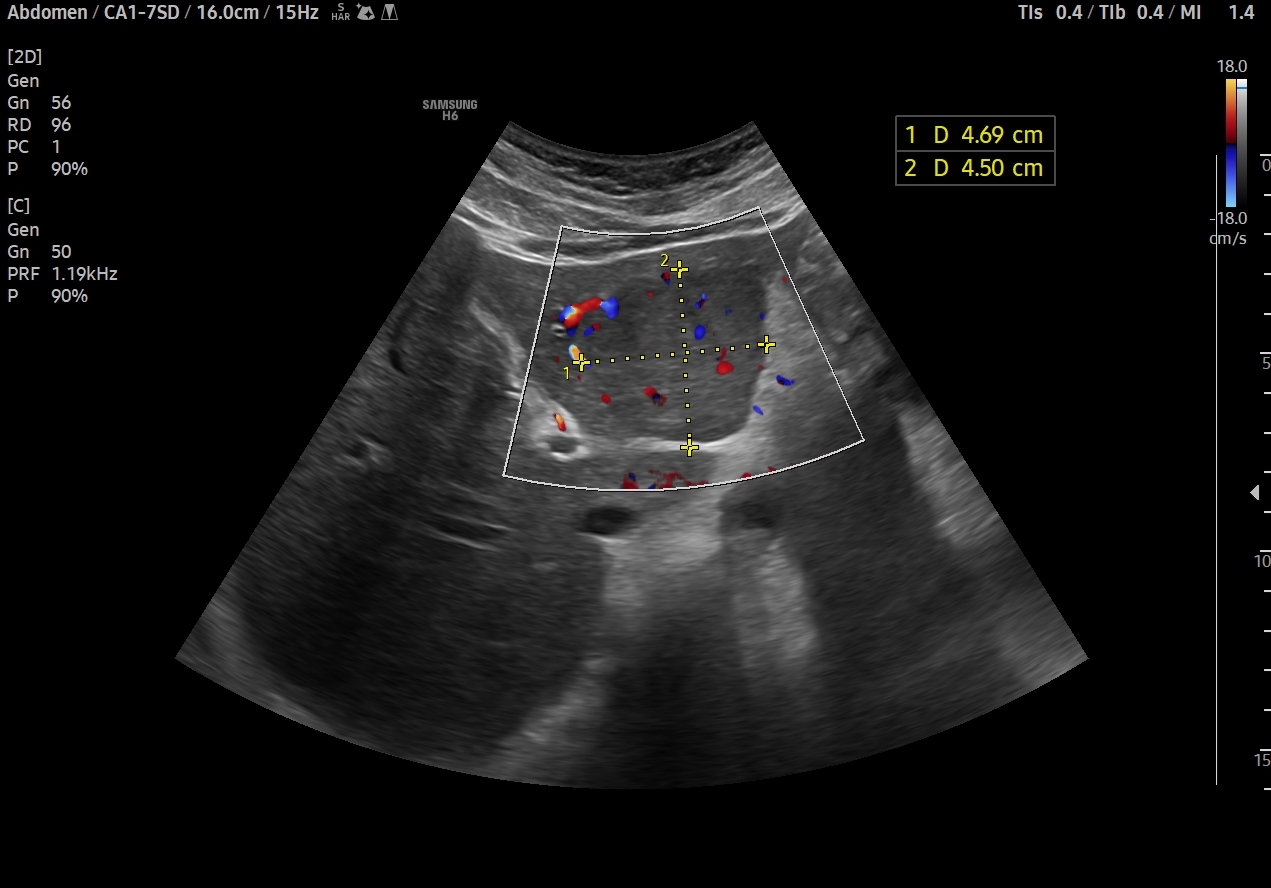

En el lóbulo hepático izquierdo visualizamos lesión focal iso-hipoecogénica respecto al parénquima hepático circundante que mide 4,6 x 4,5 x 3,9 cm y que presenta un aumento de la señal Doppler. Vemos la imagen tanto en cortes transversales como en cortes longitudinales, también con el modo Doppler activo. Resto de parénquima hepático y vía biliar de aspecto normal, sin otras alteraciones.

Solicitamos ecografía reglada, haciendo el servicio de radiología finalmente Resonancia magnénica (RM) del hígado: Lesión en el lóbulo hepático izquierdo de 40 x 42 mm, localizada fundamentalmente en el segmento III y en localización subcapsular, que dada las características es compatible con una hiperplasia nodular focal.